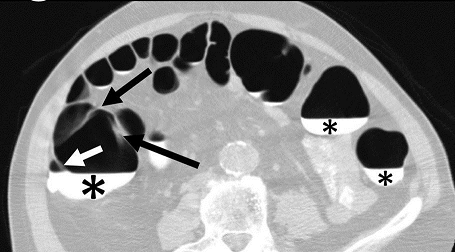

A single reviewer evaluated all data sets using a DICOM image viewer (OsiriX v4.0) for inclusion into this study. Inclusion criteria were: (1) adequate colonic distension and (2) presence of measurable folds. Having a minimum of at least five consecutive measurable haustral fold pairs in a given colonic segment was established as a marker of adequate bowel distention for optimal measurement of folds. Measurable folds were defined as folds that were not obscured or distorted by retained fluid, luminal collapse, tortuosity or diverticulosis. As haustral folds meet at the teniae coli, two of the three folds were each measured with the most dependent fold excluded; the most dependent folds were most often obscured by fluid if present (Figure 1A). Measurements of fold heights were made on 2D multiplanar reformations; the imaging plane demonstrating the folds in cross-section was established for optimal measurement of fold heights (Figure 1B). Due to the high frequency of tortuosity, suboptimal distention relative to other colonic segments, distortion of the folds and diverticulosis relative to other colonic segments, the sigmoid colon was not included in this study.

Figure 1A.Axial CT-Colonography image demonstrating dependent fluid tagging (*) obscuring a dependent haustral fold (white arrow) with a pair of unobscured, non-dependent haustral folds (black arrows). Note: difficulty in visualization of haustral fold pair due to slice selection in the axial plane.

Axial CT-Colonography image demonstrating dependent fluid tagging (*) obscuring a dependent haustral fold (white arrow) with a pair of unobscured, non-dependent haustral folds (black arrows). Note: difficulty in visualization of haustral fold pair due to slice selection in the axial plane.